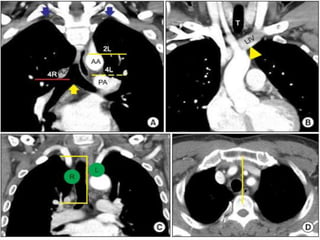

•Stage T4

tumors.

•T4 tumor due

to invasion of

pulmonary

artery (arrow,

a),

•Descending

aorta (arrow, b),

•Vertebral body

(arrow, c),

•Superior vena

cava with

thrombus

(arrow, d)

•Stage T4 tumors. •T4 tumordue to invasion of pulmonary artery (arrow, a), •Descending aorta (arrow, b), •Vertebral body (arrow, c), •Superior vena cava with thrombus (arrow, d)